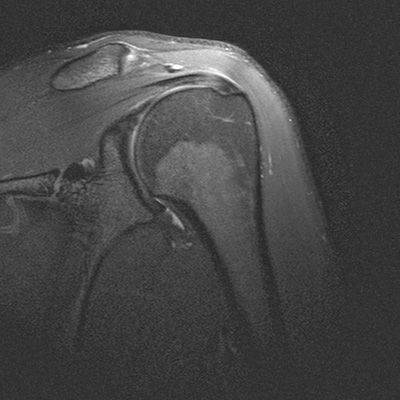

Для артроскопических вмешательств на плечевом суставе есть определенные показания. Для полноценной диагностики повреждения плечевого сустава проводится МРТ исследование. Важно, чтобы специалисты лучевой диагностики, проводящие исследование, имели достаточный опыт проведения исследований при таких патологиях. Ниже перечислены основные патологии, при которых показана операция:

Повреждения вращательной (ротаторной) манжеты плеча

Вокруг головки плечевой кости располагается несколько сухожилий, образующих вращательную или ротаторную манжету плеча. В состав манжеты входят сухожилия надостной, подостной, малой круглой и подлопаточной мышц плеча. Эти мышцы обеспечивают как стабильность головки плеча, прижимая её к суставной впадине при отведении руки (начальная фаза так и вращение плеча внутрь и снаружи. При повреждении сухожилий ротаторной манжеты (одного или нескольких), происходит нарушение механики плечевого сустава, возникают ограничения подвижности, боли при отведении руки.